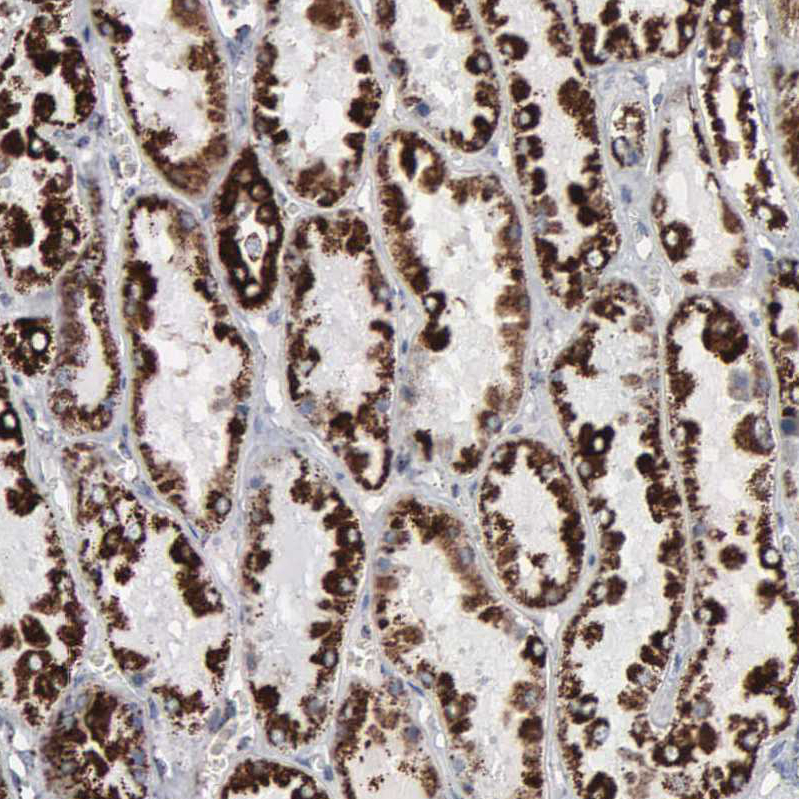

Immunohistochemical staining of human kidney shows strong positivity in mitochondria in cells in tubules.